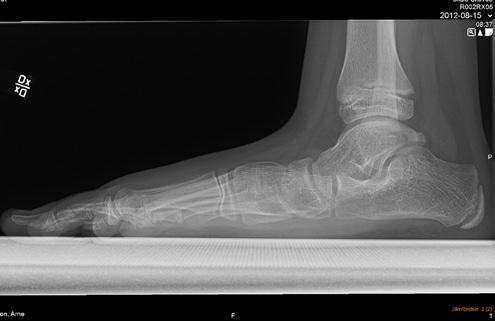

Sannolikt normalt/fysiologiskt hos barn om den är bilateral. Plattfothet undersöks bäst bakifrån när barnet står på hela foten och sedan ställer sig på tå. Då ser man hur bakfoten går från valgus vid belastning till varus vid tåstående. Likaså kan man se att det utvecklas ett längsgående medialt fot valv när barnet ställer sig på tå jämfört med när hela foten belastas. Se bild 1.

Sannolikt. Plattfotheten beror nog mest på flexibla fötter som inte har något strukturellt fel. Observera att det normala är bilateral plattfothet. Unilat eral betyder att en fot är platt, pes plano valgus, eller att den andra är i varus, ibland cavo varus, vilket inte är normalt. Om det finns en tydlig asym metri och fotfelställningen är förvärvad behöver man tänka på möjlig neuropati eller pro cess i spinalkanalen. Se bild 2.

Plattfothet är en felställning i första hand och inte en diag nos. En individuell bedömning av var felställningen sitter och vad den kan bero på behövs. Se bild 3.